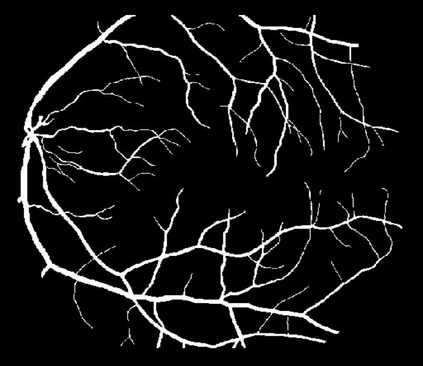

Image segmentation is a fundamental task in image analysis and clinical practice. The current state-of-the-art techniques are based on U-shape type encoder-decoder networks with skip connections, called U-Net. Despite the powerful performance reported by existing U-Net type networks, they suffer from several major limitations. Issues include the hard coding of the receptive field size, compromising the performance and computational cost, as well as the fact that they do not account for inherent noise in the data. They have problems associated with discrete layers, and do not offer any theoretical underpinning. In this work we introduce continuous U-Net, a novel family of networks for image segmentation. Firstly, continuous U-Net is a continuous deep neural network that introduces new dynamic blocks modelled by second order ordinary differential equations. Secondly, we provide theoretical guarantees for our network demonstrating faster convergence, higher robustness and less sensitivity to noise. Thirdly, we derive qualitative measures to tailor-made segmentation tasks. We demonstrate, through extensive numerical and visual results, that our model outperforms existing U-Net blocks for several medical image segmentation benchmarking datasets.